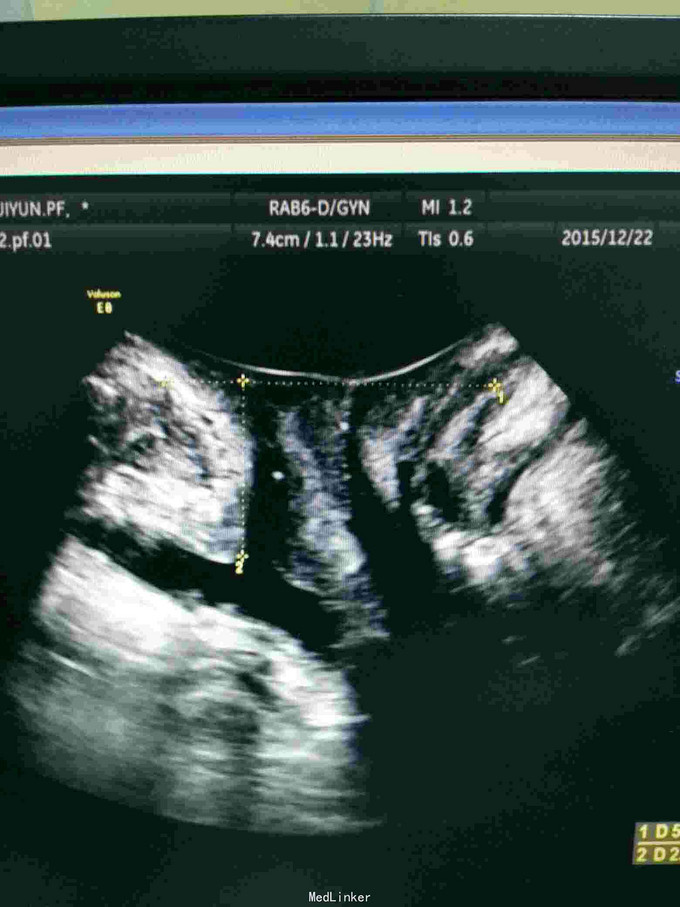

查体:双肾区无红肿、隆起,无叩痛,双侧肋脊点、肋腰点无压痛。尿道口可见大小约3mm息肉,未见盆腔脏器脱出。 辅查:2015-12-8清远市中医院IVP未见明显异常;胸片提示主动脉硬化;泌尿系B超未见异常;膀胱镜检提示膀胱憩室,左右侧壁各1个,分别约2*3cm、3*4cm;尿道口息肉。